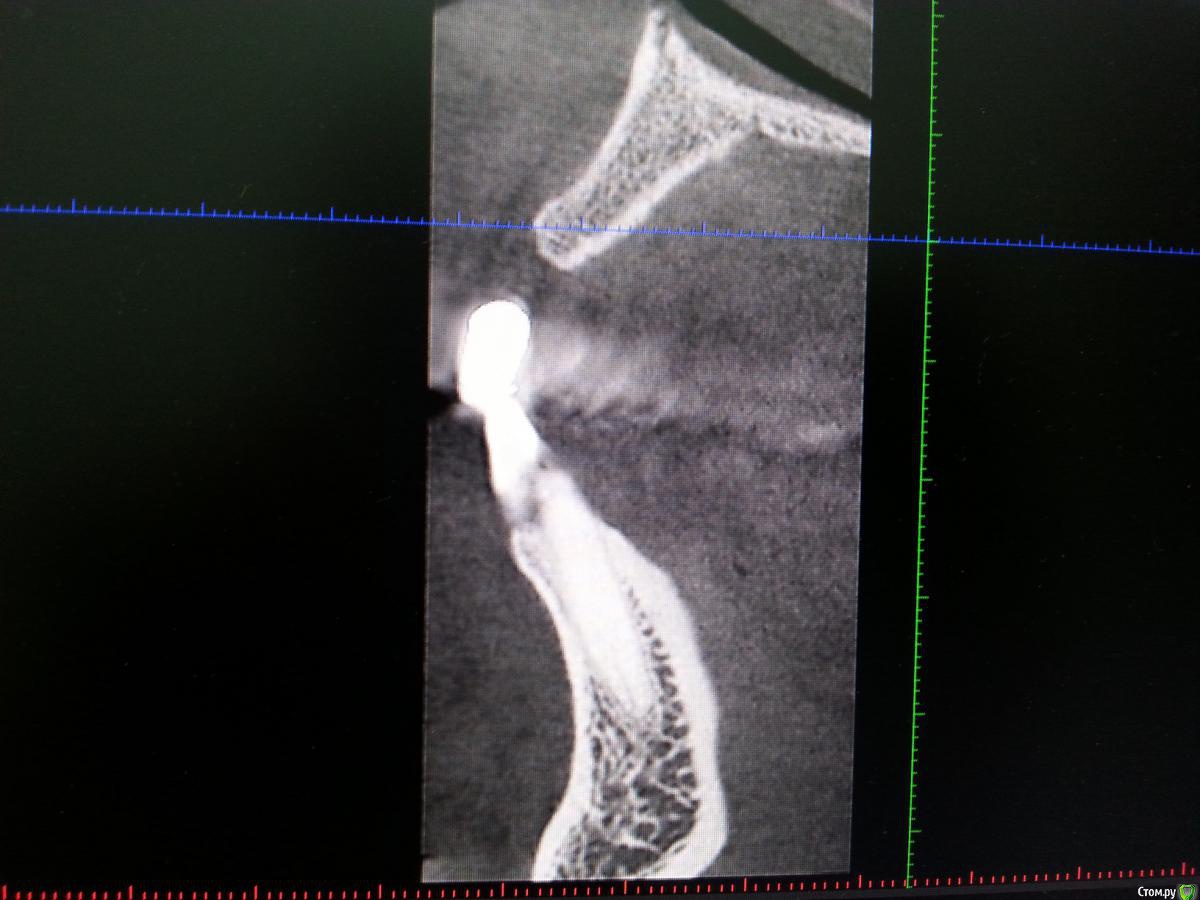

Zamber Опубликовано 29 декабря, 2016 Автор Поделиться Опубликовано 29 декабря, 2016 Сегодня показал врачу КТ. Одномоментная имплантация не грозит теперь точно, поскольку кость практически отсутствует. Выкладываю некоторые фрагменты, надеюсь на комментарии. Могут ли здесь быть шансы? Ссылка на комментарий

Zamber Опубликовано 30 декабря, 2016 Автор Поделиться Опубликовано 30 декабря, 2016 Я бы вел отсрочено Мне предложили костную пластику, а затем - в зависимости от результата. Это для 11 (тот, что на КТ). У 12 толщина кости 4,6, предлагают имплантировать. Толщины достаточно? Ссылка на комментарий

red_butler Опубликовано 30 декабря, 2016 Поделиться Опубликовано 30 декабря, 2016 У 12 толщина кости 4,6, предлагают имплантировать. Толщины достаточно? покажите срезы Кт Ссылка на комментарий

Zamber Опубликовано 30 декабря, 2016 Автор Поделиться Опубликовано 30 декабря, 2016 покажите срезы Кт Кажется, этот Ссылка на комментарий

red_butler Опубликовано 30 декабря, 2016 Поделиться Опубликовано 30 декабря, 2016 Да здесь ситуация лучше. Ссылка на комментарий